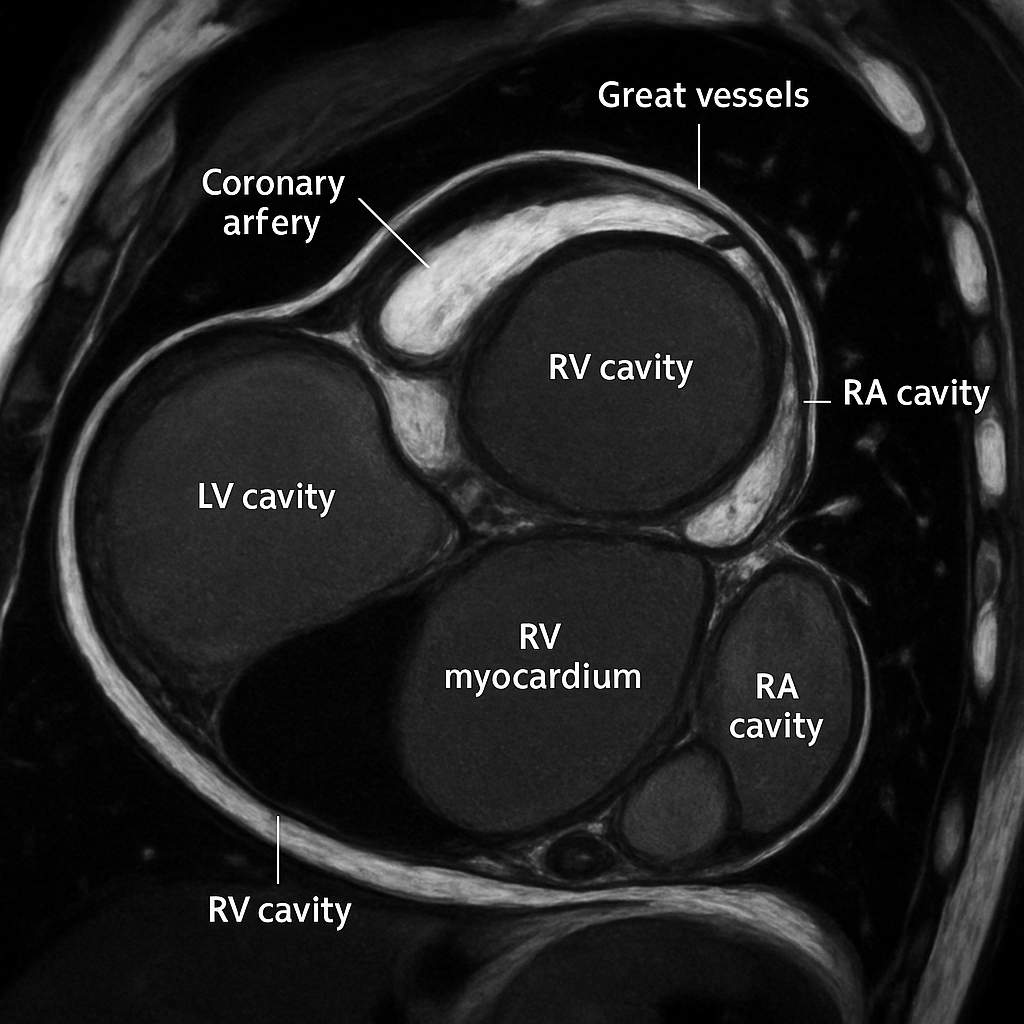

MRI — Short Axis Cine (Diastole)

Cardiac MRI short-axis (SA) view at mid-ventricular level during end-diastole. Balanced SSFP sequence showing bright blood in LV and RV cavities, dark myocardium, papillary muscles.

Ssfp Short Axis

bSSFP cine, mid-ventricular short axis, end-diastolic frame. Bright blood pool, dark myocardium.